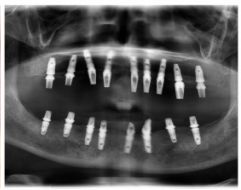

種牙后X光片,未戴冠。

通過X光片可以看到,醫(yī)生雖然盡量設(shè)計(jì)連冠種植,但還是用了十七個(gè)植體,盡管已經(jīng)是多次調(diào)整后的精簡(jiǎn)方案,但手術(shù)時(shí)長(zhǎng)依然長(zhǎng)達(dá)一天。位老先生之前在另一家醫(yī)院咨詢時(shí),醫(yī)生給的方案是種二十二個(gè)植體,光是種植費(fèi)用就令人大呼“害怕”了。

種牙前X光片

種植修復(fù)后X光片